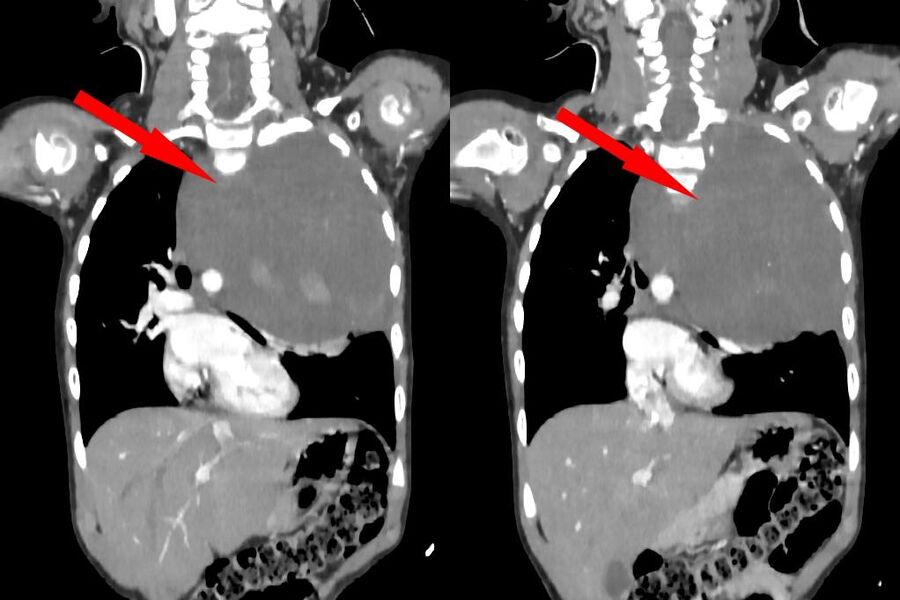

Родители показали дочь врачам, когда заметили у нее небольшую припухлость в области шеи. Специалисты по месту жительства выявили огромное новообразование размером со страусиное яйцо, которое сдавливало сердце и легкое. Сквозь ткань опухоли проходили крупные сосуды: «позвоночная артерия, питающая головной мозг, и подключичная артерия с ее ветвями, питающая левую руку». После телемедицинской консультации ребенка направили в Москву.

«Учитывая гигантский размер опухоли и ее расположение вблизи множества жизненно важных структур, мы использовали расширенный доступ по типу «раковины моллюска». Он предполагает рассечение не только межреберного промежутка, но и самой грудины, что позволяет «раскрыть» грудную клетку, как раковину», — рассказал заведующий отделением реконструктивной и восстановительной хирургии грудной полости РДКБ, к.м.н. Евгений Андреев об операции.